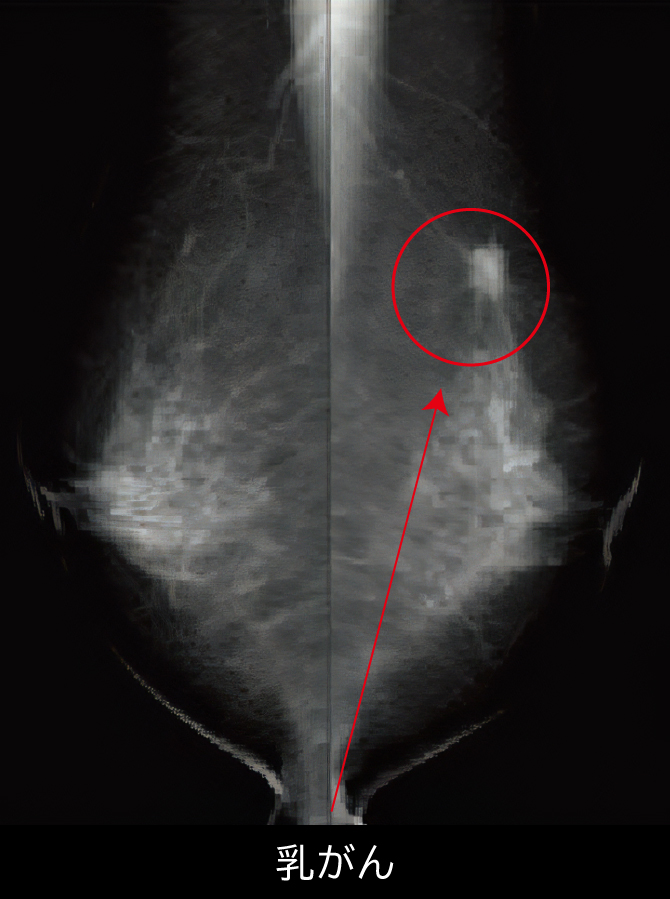

乳房X線検査(マンモグラフィ)

この検査を含む項目

乳がんは30歳代から増加し始め、日本人女性の9人に1人が乳がんにかかると報告されています。

マンモグラフィは乳がん検診において死亡率減少効果が認められている検査方法で、

乳房を片方ずつ押さえ、乳腺を広げてX線で撮影する検査です。注意事項